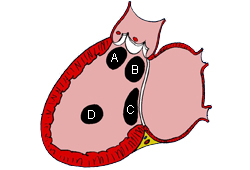

Subtipos de comunicaciones interauriculares: (A) seno venoso; (B) ostium secundum; (C) ostium primum; (D) seno coronario sin techo